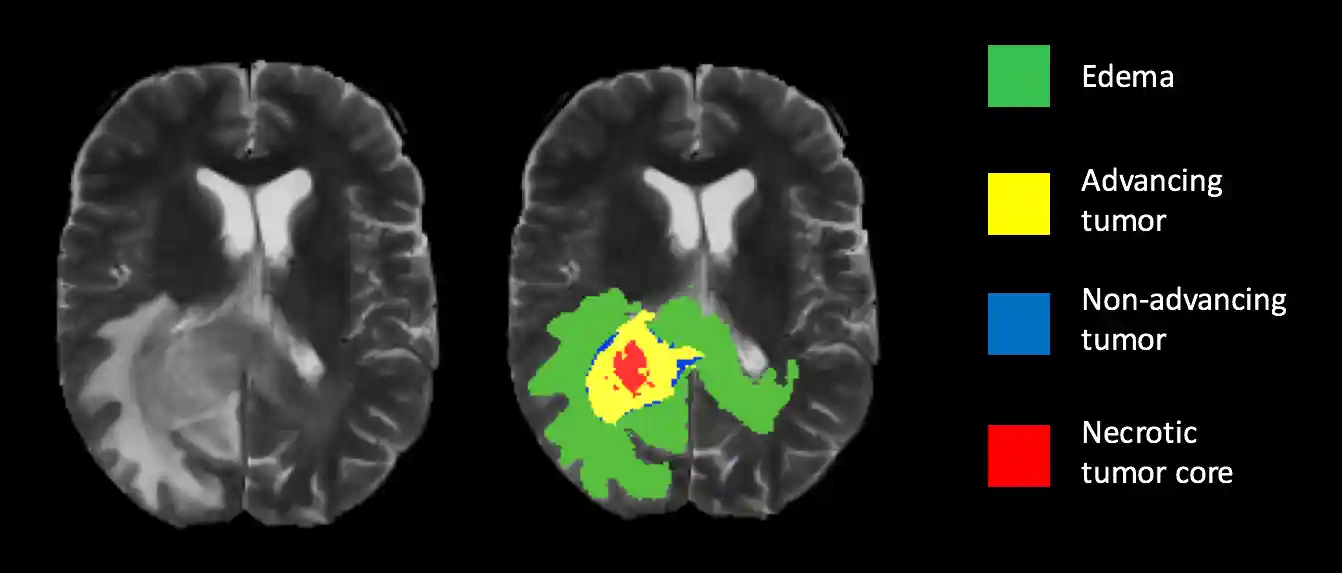

Brain tumor segmentation seeks to separate healthy tissue from tumorous regions such as the advancing tumor, necrotic core and surrounding edema. This is an essential step in diagnosis and treatment planning, both of which need to take place quickly in the case of a malignancy in order to maximize the likelihood of successful treatment. Due to the slow and tedious nature of manual segmentation, there is a high demand for computer algorithms that can do this quickly and accurately.

All MRI data was provided by the 2015 MICCAI BraTS Challenge, which consists of approximately 250 high-grade glioma cases and 50 low-grade cases. However, due to the limited time Each dataset contains four different MRI pulse sequences, each of which is comprised of 155 brain slices, for a total of 620 images per patient. Professional segmentation is provided as ground truth labels for each case. Figure 1 is an example of a scan with the ground truth segmentation. The segmentation labels are represented as follows:

Figure 1: Ground truth segmentation overlay on a T2 weighted scan.MRI Background